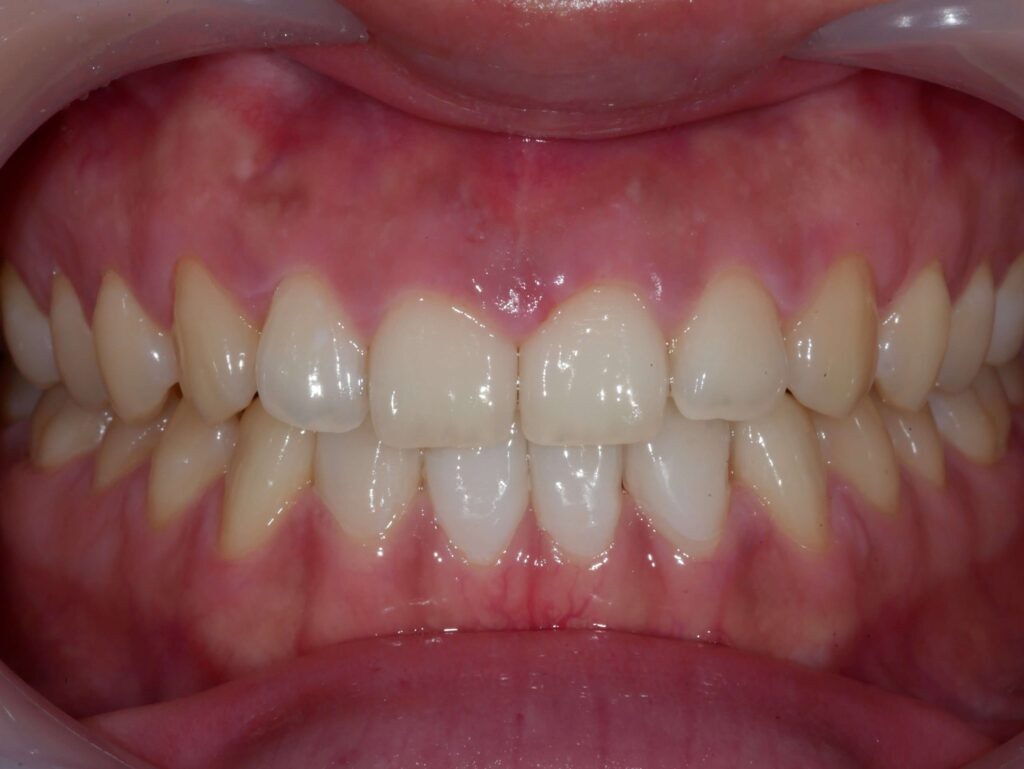

치료 전후 사례